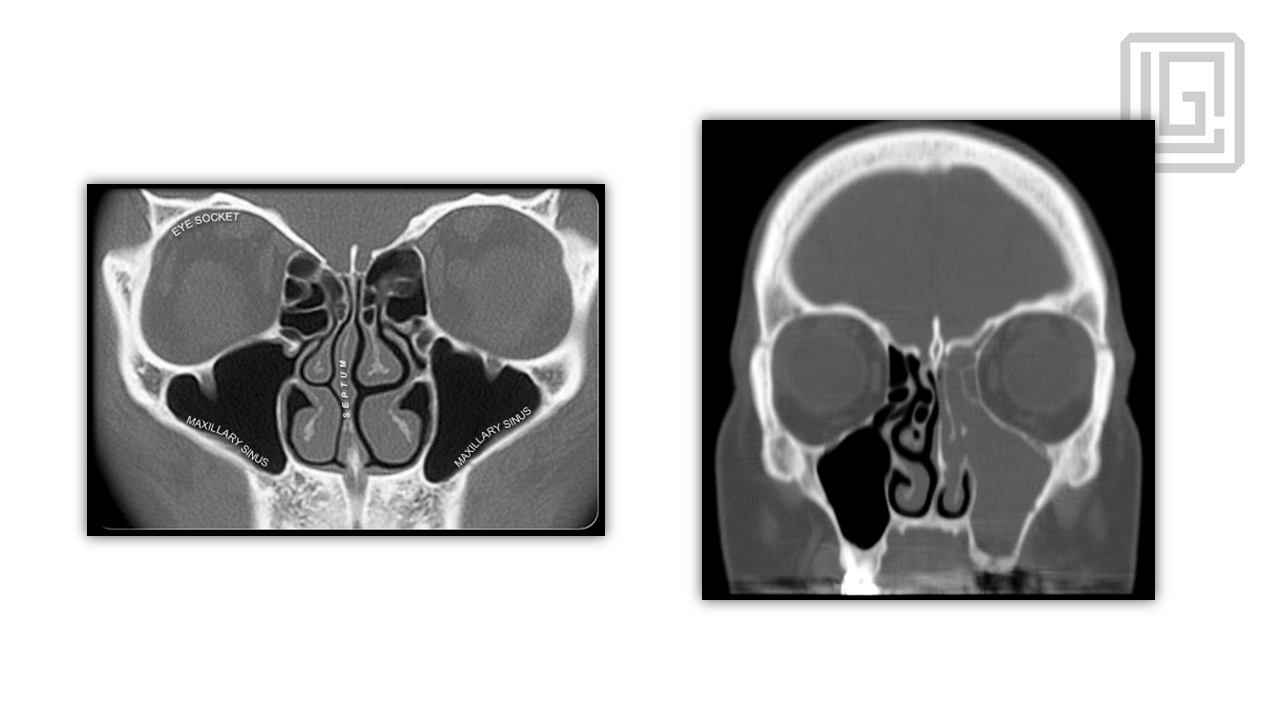

In-depth presentation on the pathophysiology of chronic rhinosinusitis, radiologic planning, sinonasal anatomy, and step-by-step FESS surgical protocol. Covers infundibulum, osteomeatal complex, surgical landmarks, instrumentation, complications, and postoperative management. Presented by Dr. Levon Galstyan.